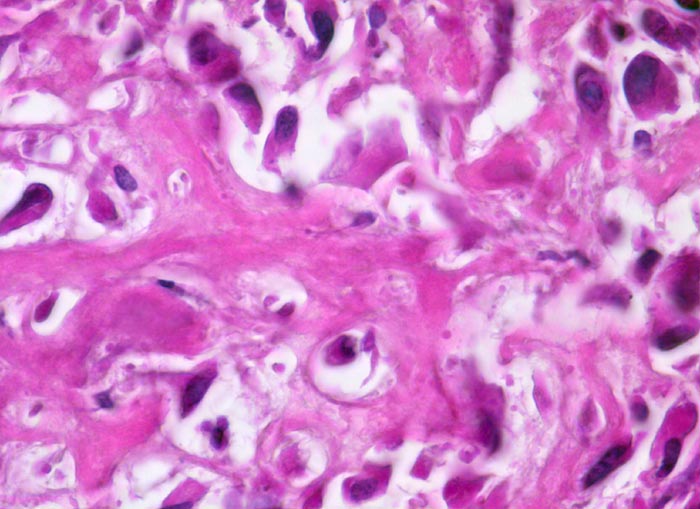

Osteosarkom

Netz aus schmalem, verzweigtem, teils verkalktem, neugebildetem Tumorosteoid, das direkt von stark polymorphen mesenchymalen Tumorzellen mit hyperchromatischen Kernen gebildet wird. Die Zytomorphologie ist nach Entkalkung nur eingeschränkt beurteilbar.

Der Nachweis von Osteoid, das von atypischen Zellen gebildet wird, ist das wichtigste Kriterium für die Diagnose eines Osteosarkoms. Osteosarkome können aber auch auf weiten Strecken ausschliesslich chondroide oder fibröse Matrix bilden und dann ein Fibrosarkom, Chondrosarkom oder ein malignes fibröses Histiozytom imitieren.